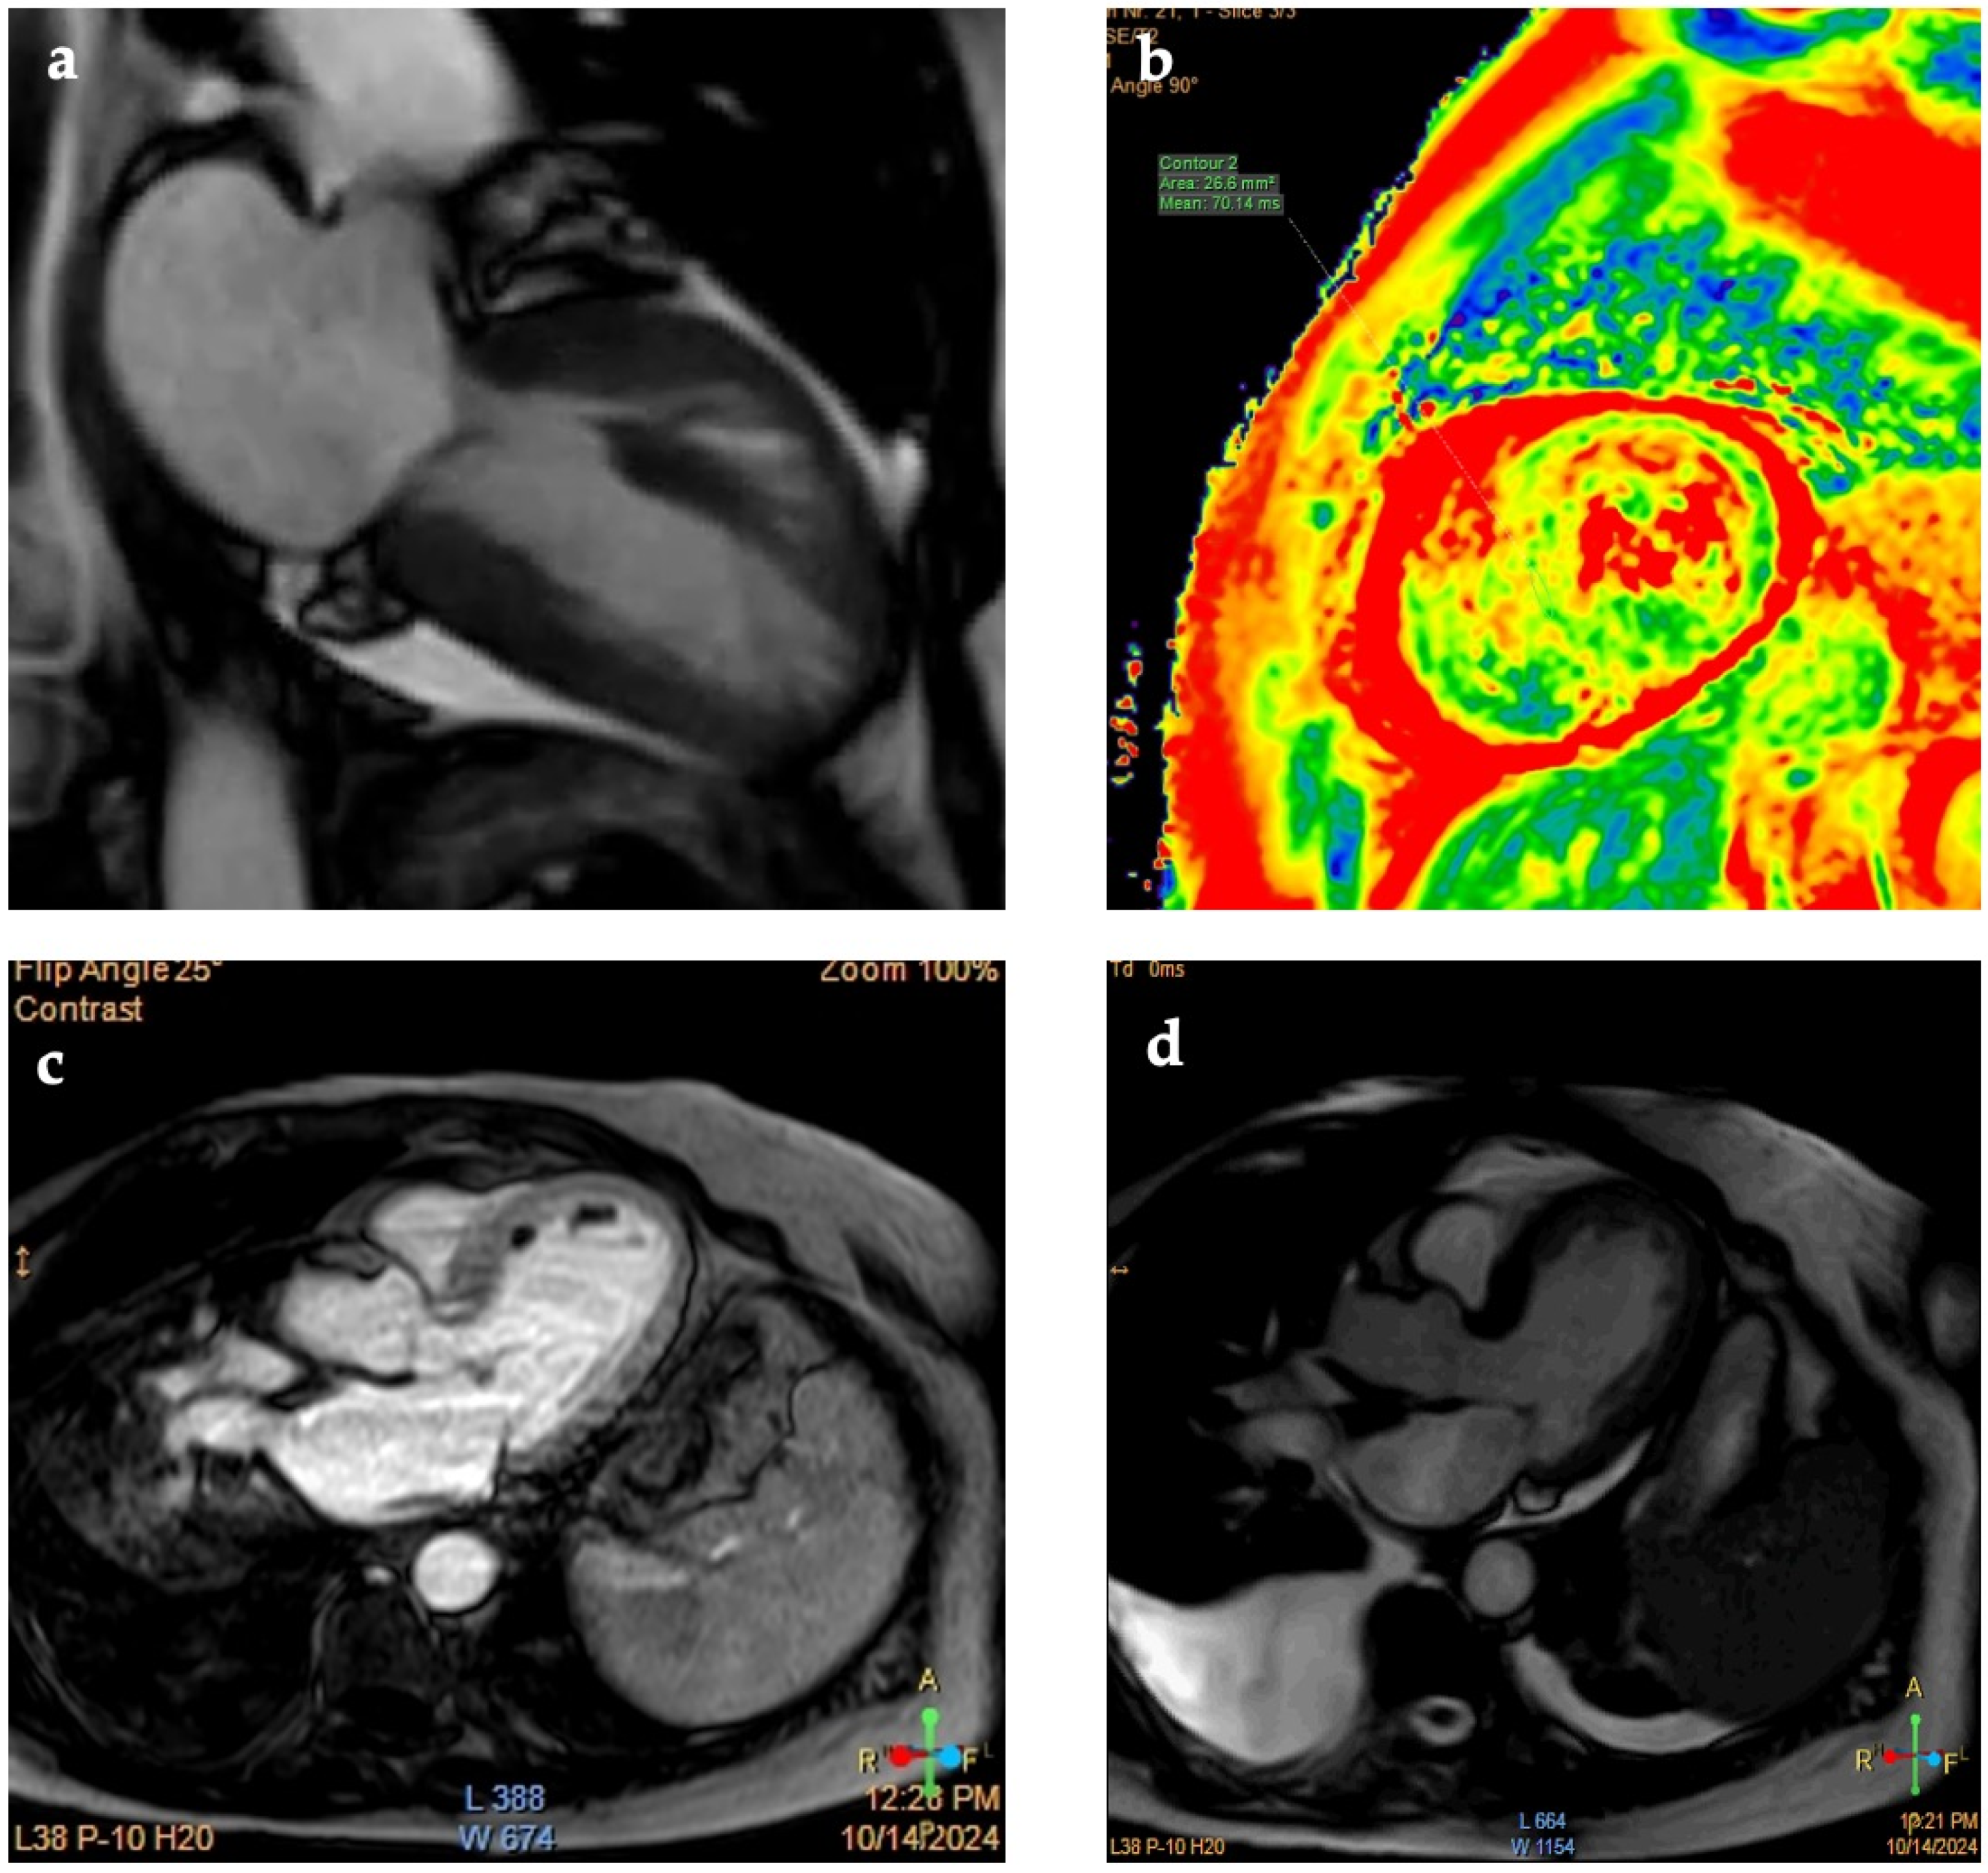

| CMR | High-signal T2 (edema) Global/regional wall motion abnormalities Non-specific distribution of LGE | High-signal T2 (edema) Regional wall motion abnormalities Absence (usually) of LGE in the acute stage |